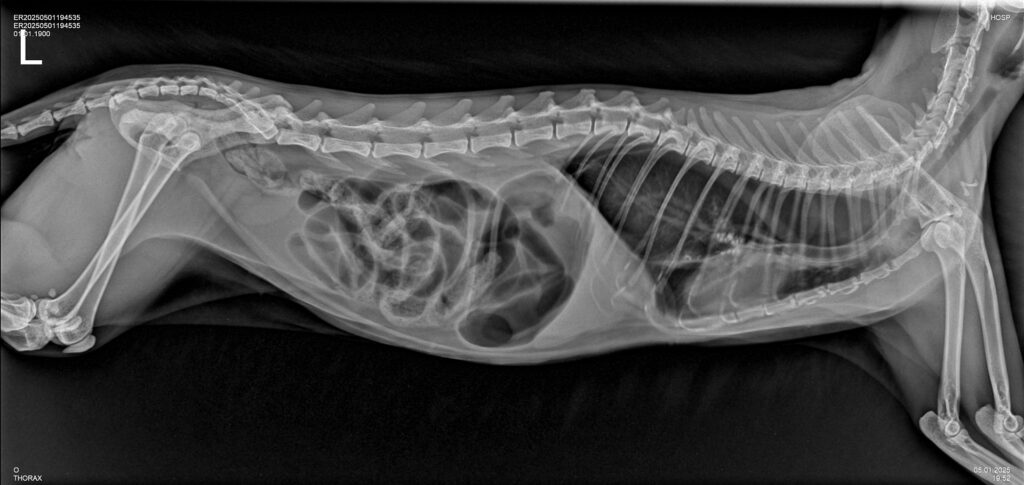

Одним из самых современных и информативных методов диагностики в ветеринарии является рентгенография. В клинике «Умная ветеринария» данный метод исследования проводится для постановки диагнозов при различных заболеваниях животных на цифровом рентген-аппарате высокого класса, позволяя ветеринарным врачам клиники получать ценную информацию о здоровье животных и назначать эффективные варианты лечения.

В ветеринарии рентгенография — это универсальный и незаменимый вид диагностики, один из самых точных, удобных, экономически выгодных для потребителя услуг неинвазивных методов диагностических исследований, используемый для визуализации внутренних структур животных.

Благодаря цифровой рентген-диагностике специалисты «Умной ветеринарии» получают быстрое изображений интересующей области исследования в виде снимка высокого качества на экране монитора, при этом современный цифровой рентген-аппарат, установленный в клинике, адаптирован под нужды ветеринарии, имеет специальное ветеринарное назначение и излучает минимально низкую дозу рентгеновского излучения для пациента, его владельцев, а также для специалиста рентген-кабинета.

Технология рентгенографии основана на использовании рентгеновских лучей, которые проникают через ткани животного. За небольшое количество времени излучение проходит сквозь мягкие ткани, такие как мышцы и внутренние органы, затем оно частично поглощается плотными структурами, такими как кости. Это позволяет получить высокоточное изображение скелета и органов тела животного.

- Рентген-диагностика у животных на определение беременности и количества плодов. В отличие от людей, у животных рентген-диагностика активно применяется в случаях, когда необходимо не только подтвердить или исключить факт наступления беременности у животного, но и с большей точностью, чем при УЗ-диагностики, определить количество плодов при беременности. Именно цифровая рентгенография полностью безопасна для самой будущей матери и ее потомства в этом случае.

Во время процесса рентгенографии рентгеновские лучи фиксируются на цифровой панели, создавая темный силуэт скелета животного на белом фоне. Мягкие ткани, внутренние органы, отображаются в виде различных оттенков серого в зависимости от их плотности.